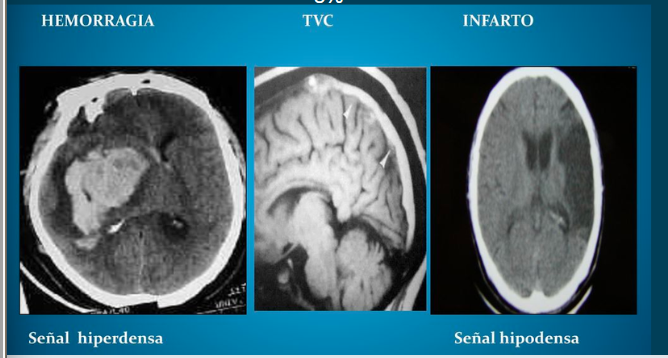

TC

Estudio para identificar rápidamente el sangrado intracraneal e isquemia cerebral aguda.

TC (tomografía computarizada)